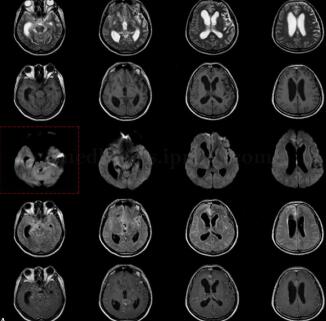

患者男,43岁,外院检查示颅内病变性质待查(图1)。

图1 脑底池结构显示不清,双侧颞叶脑回皮质增厚并呈长T2信号,脑沟增宽。左侧基底节区见斑点状长T1、长T2信号影。弥散加权左侧颞极见斑片状高信号。幕上脑室扩大,尤以右侧为著。中线结构居中。增强:室管膜、中线处脑膜、左侧外侧窝池多发结节样强化影